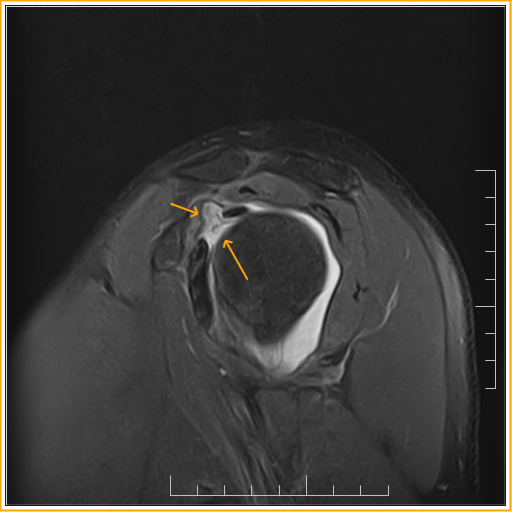

Adhesive capsulitis in a 59yearold patient. (a) Oblique sagittal PDw Adhesive Capsulitis With Rotator Cuff Tear — adhesive capsulitis (also known as frozen shoulder) is a condition of the shoulder characterized by functional loss of both passive and. — frozen shoulder, also called adhesive capsulitis, is a condition involving pain and stiffness in your shoulder joint. — frozen shoulder is also referred to as adhesive capsulitis, painful stiff shoulder, and periarthritis. —. Adhesive Capsulitis With Rotator Cuff Tear.